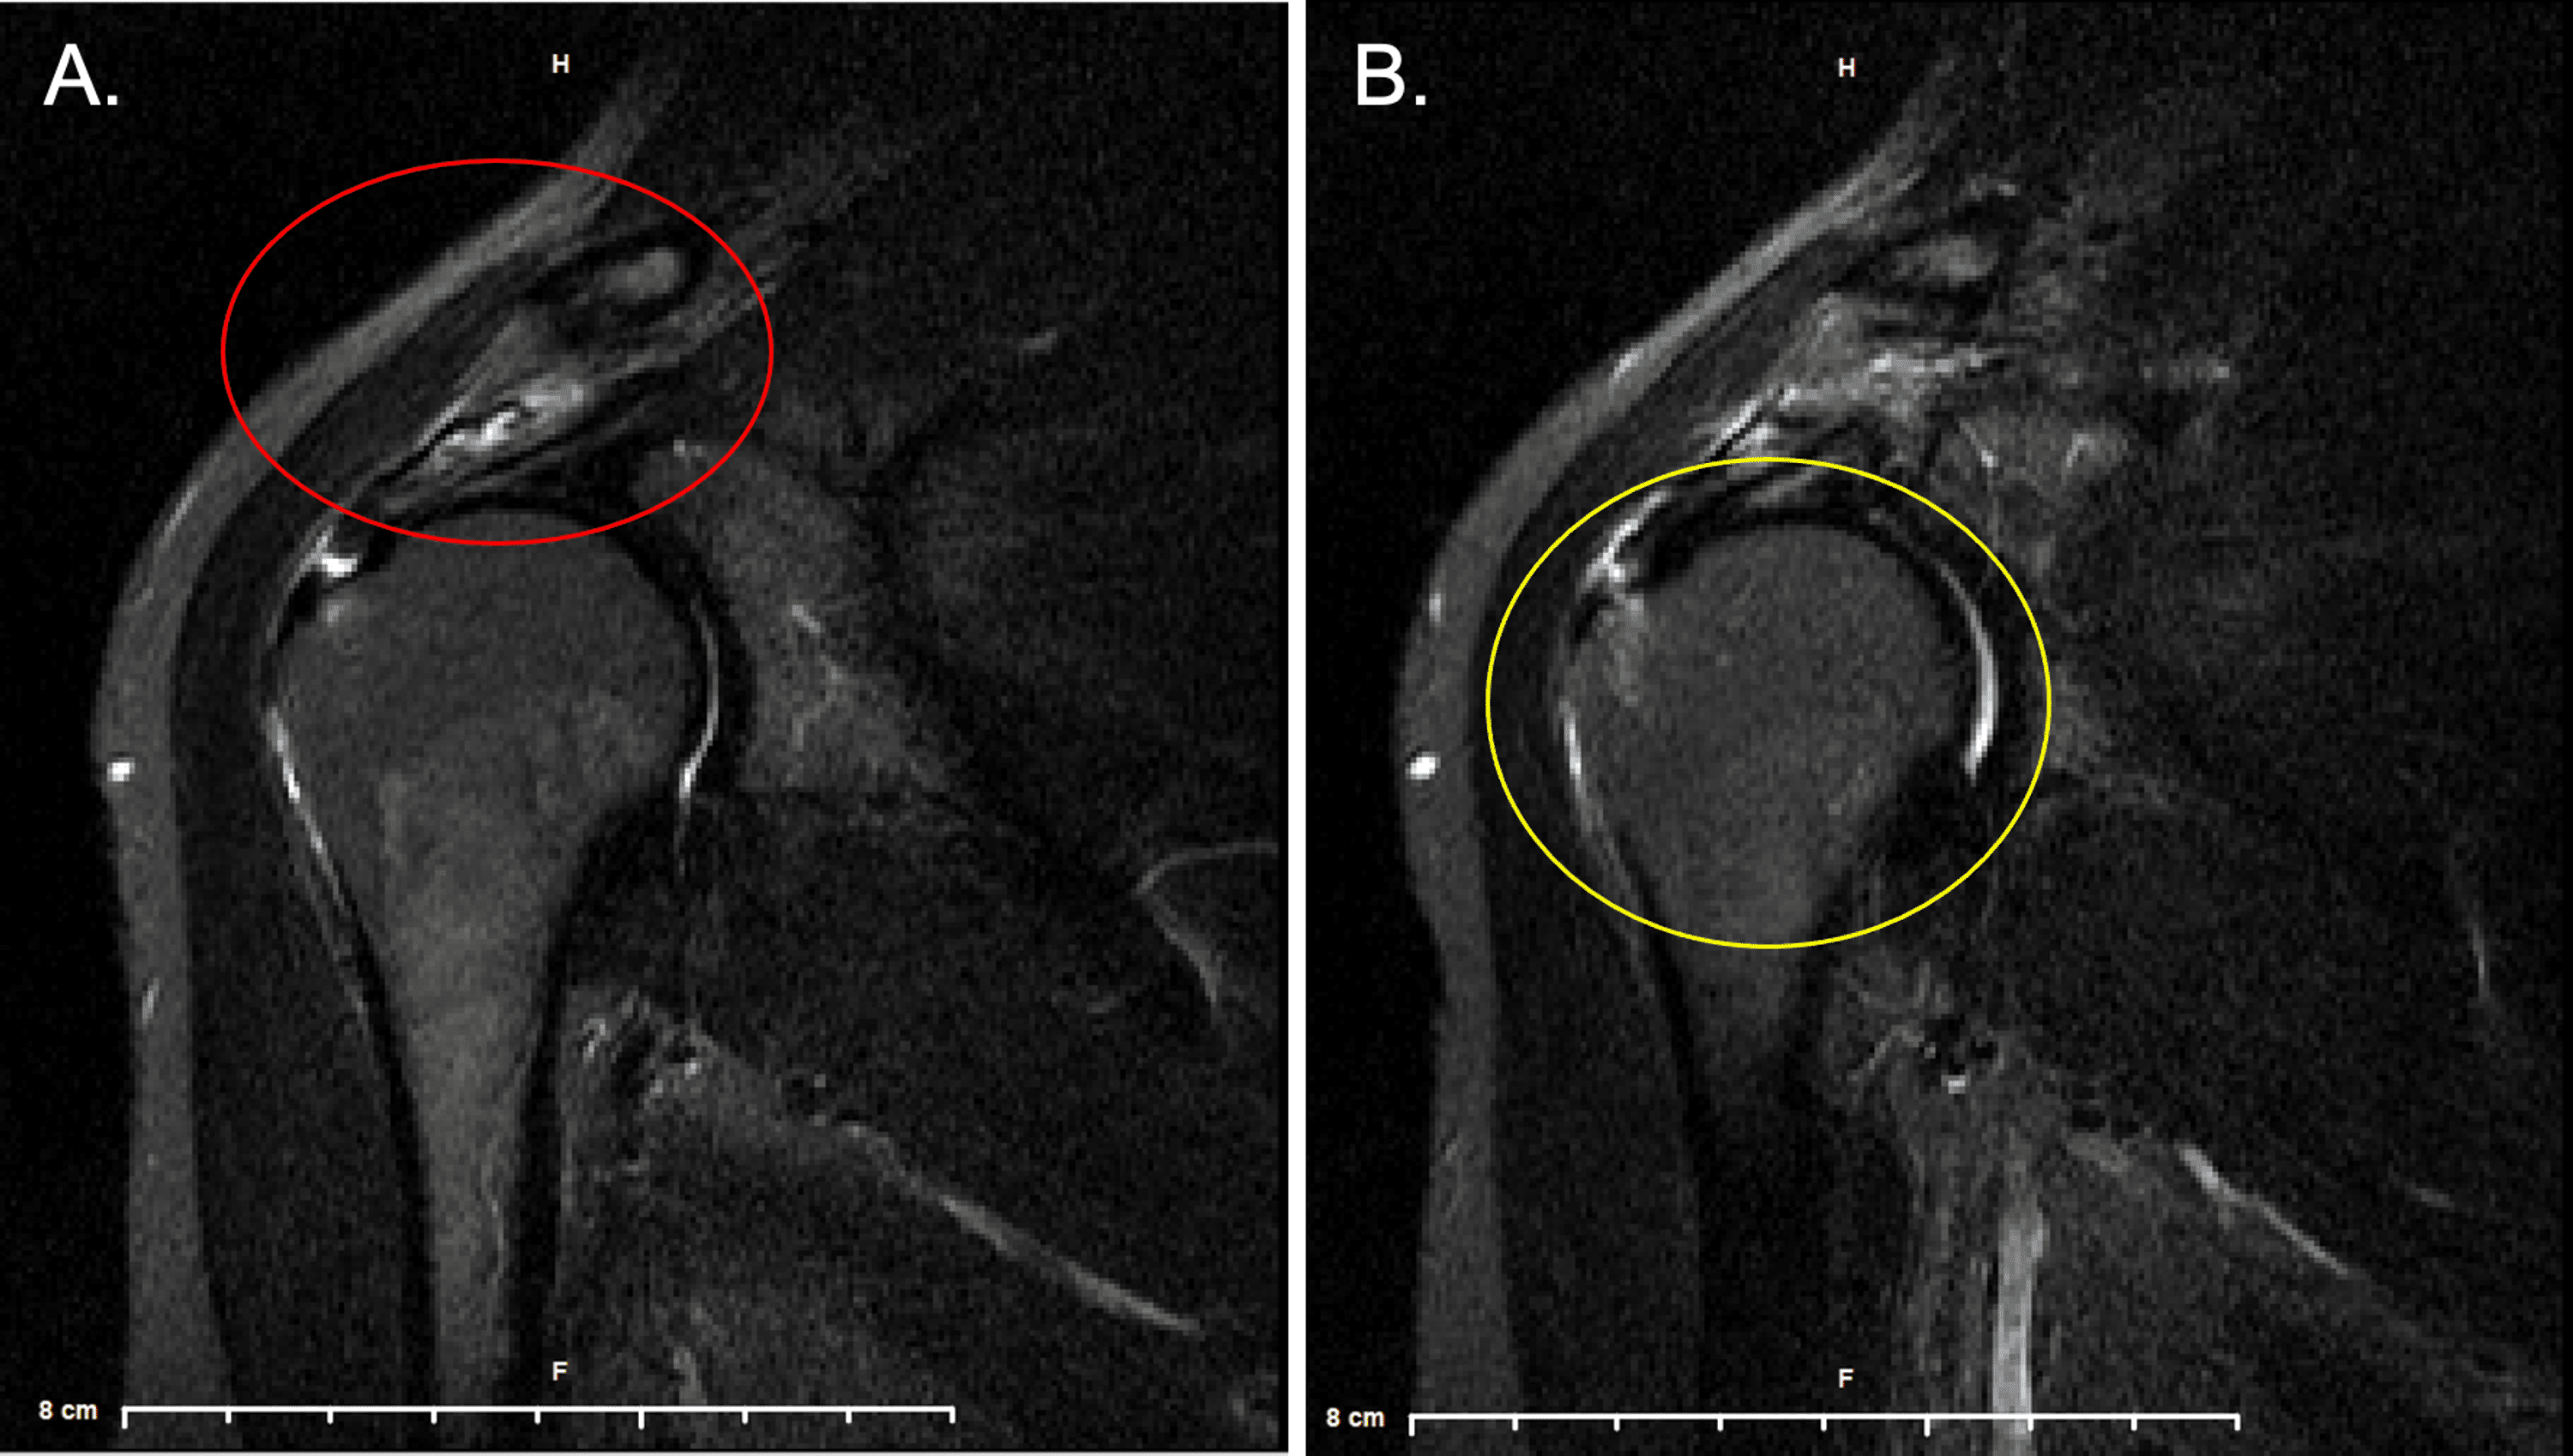

From www.cureus.com

Osteopathic Manipulative Treatment for a Chronic Rotator Cuff Tear A Rotator Cuff Tear Urgent Care This article provides answers to. In many cases, physical therapy also may help. rotator cuff injury is a common cause of shoulder pain, especially in older and active people. the rotator cuff tendons cover the head of the humerus (upper arm bone), helping you to raise and rotate your arm. when a rotator cuff tear is minor,. Rotator Cuff Tear Urgent Care.